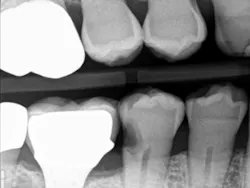

When decay arises on adjacent teeth, dentists must evaluate their treatment options. I have found there is a high degree of difficulty restoring large Class II or interproximal lesions with direct composites, especially when the decay is on premolars. It is much more predictable to restore Class IIs on molars with tight contacts, but it can still be difficult. I have tried full matrix bands and multiple sectional matrix bands, but I can’t create a nice contour with a tight contact. I have even tried traditional composites and bulk fill without great success. See Figures 1 and 2 showing my open contacts with direct composite.